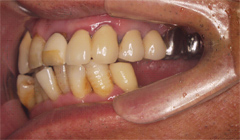

奥歯がない(65歳男性)―入れ歯で噛めない―インプラント治療後、咬合改善定期的なメインテナンスを

奥歯に入れている「入れ歯が合わない、噛めない」 患者様の症例

吉本歯科医院では、口内写真とパノラマレントゲンを撮影し、まずは顎の骨の状態まで詳しく確認しました。

写真(1)口内写真